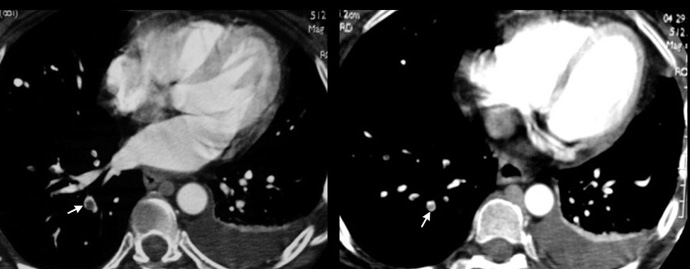

CT at the level of left atrium showing segmental emboli.

CT below the level of left atrium showing subsegemental emboli.